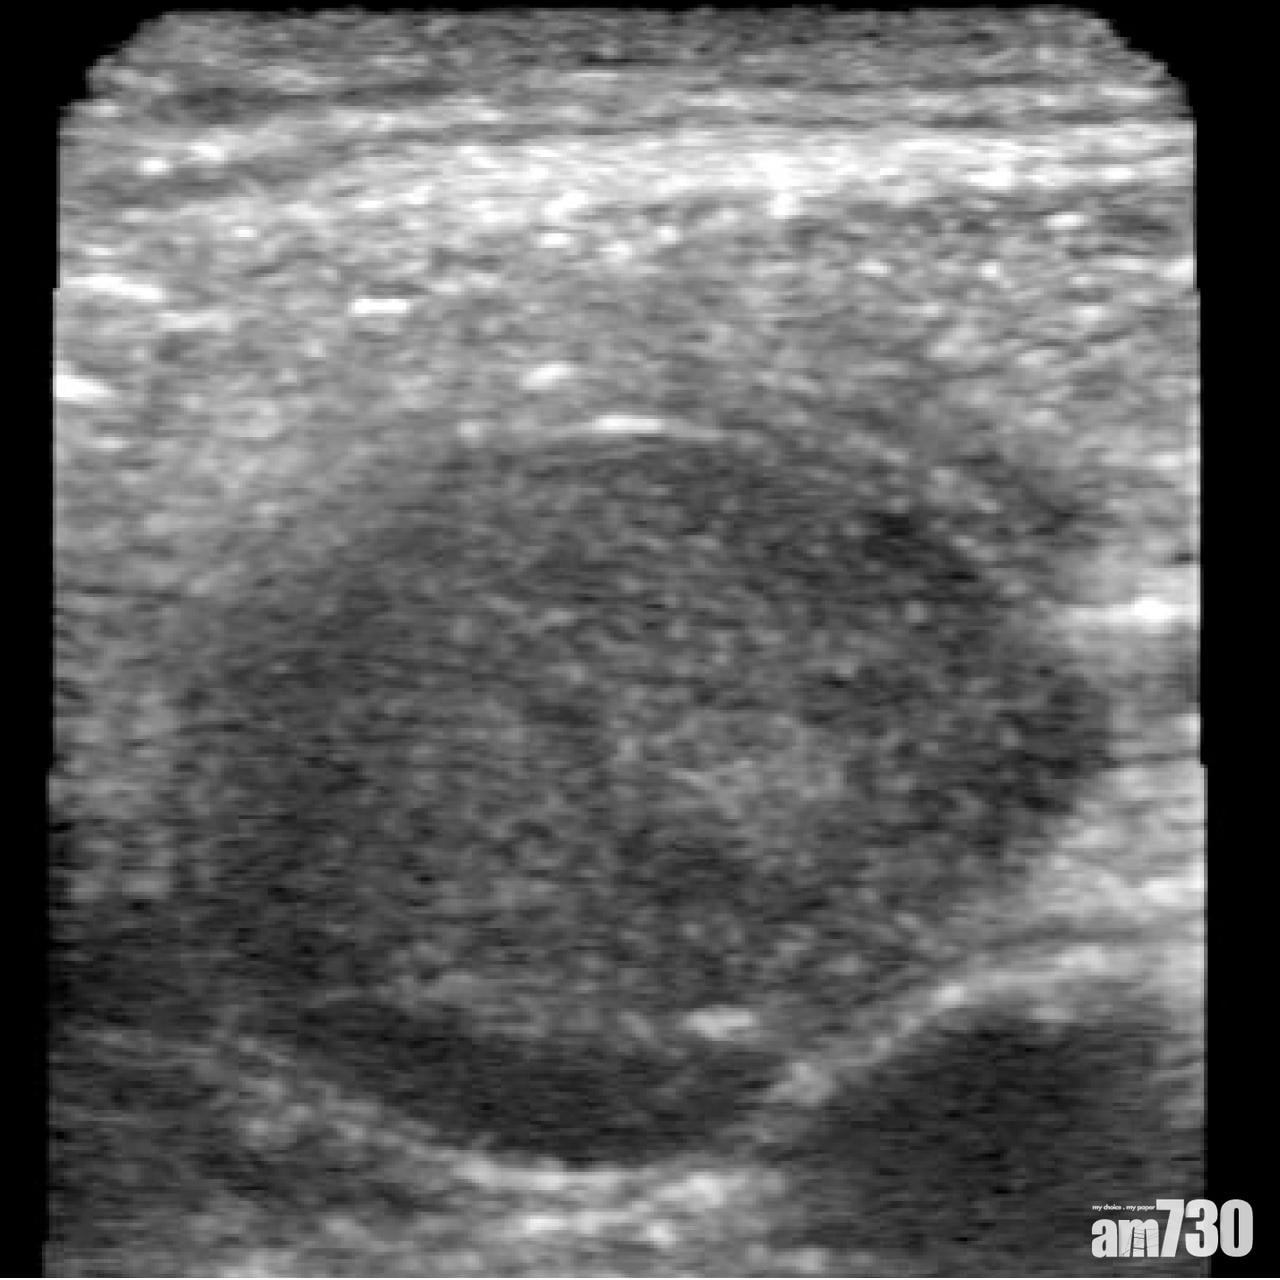

59歲血管外科醫生馬田(John Martin)宣稱,今年7月他有感喉嚨似有異物,遂以其公司發明的超聲波儀Butterfly iQ檢查頸部,果見直徑約3公分腫瘤,進一步化驗確診患皮膚癌之一的「鱗狀細胞癌」,其後接受電療及5個半小時手術控制病情,揚言該儀器有助他盡速求醫。

手機屏幕顯示超聲波影像。